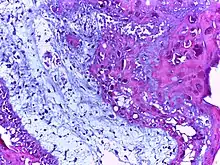

![]() | Squamous cell carcinoma of cervix | Invasive Squamous Carcinoma of the Cervix. Cold Knife Cone. | Category: Histopathology of squamous cell carcinoma of the cervix | Invasive squamous carcinoma of cervix |